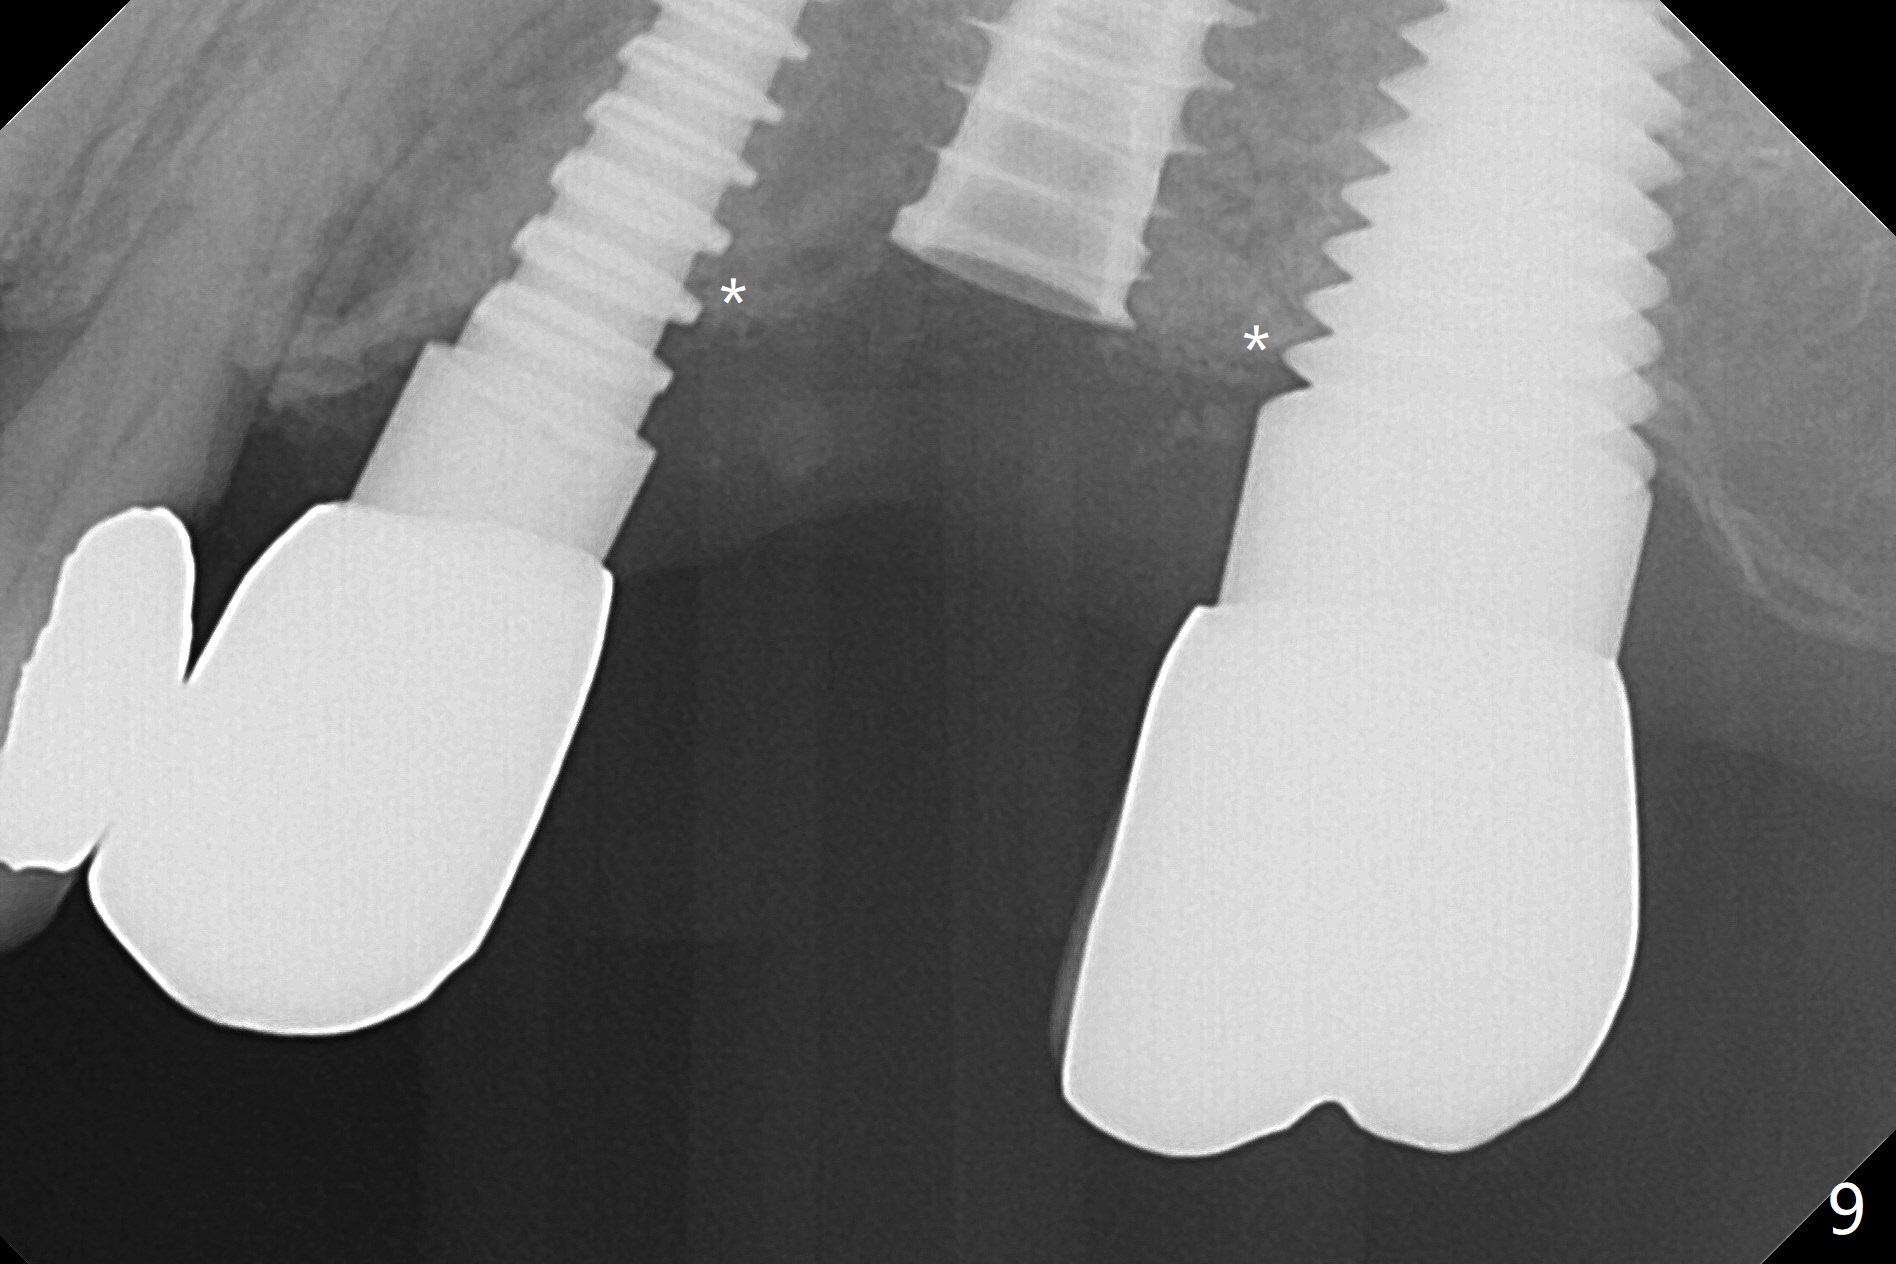

Initial osteotomy in the septum of the tooth #14 is 9 mm, approximately 2 mm from the sinus floor (Fig.1). Subsequent osteotomy depth is 11 mm, followed by insertion of a 4.5x11 mm dummy implant (Fig.2). After use of Magic Drill (MD) 4.8 mm for 9 mm, a 5x11 mm IBS implant is placed with sinus lift without additional bone graft (Fig.3 *). In contrast, autogenous bone (from MD) and Vanilla Graft are meticulously placed in the remaining socket (+) before and after placement of a 6.5x5.7(2) mm abutment. An immediate provisional is fabricated to close the sockets. There is buccal tenderness 1-3 months postop. There is distopalatal implant thread exposure. A healing abutment (5.5x2 mm) is placed. CT confirms thin buccal plate (Fig.4,5). It appears that the implant should have been as palatal as possible. The tenderness remains for the next 2 weeks. When the healing abutment is removed, the implant seems to have been placed shallow, ~ 1 mm subgingival (Fig.6). With local anesthesia, the implant is reversed to clean the coronal threads with Titanium brush and copious irrigation (Fig.7). The implant is then placed ~4 mm subgingival (Fig.8) and slightly subcrestal (Fig.9,10). It appears that the postop bone loss (Fig.9 *, as compared Fig.1,2) makes the implant look to be placed too shallow. When the implant is being placed deeper, the buccal plate feels intact. The early periimplantitis is apparently due to postop bone loss more than buccal placement, although certain degree of buccal bone resorption must occur. A 6x4 mm healing abutment is placed. Left facial swelling develops 2 days post implant elevation (Fig.11,12, as compared to preop (Fig.13)). The left maxillary sinus cloud (Fig.12) appears to be a false positive finding, since the same feature exists prior to implant elevation (Fig.13). Both sinuses look clear prior to implant elevation (Fig.14). Amoxicillin switches to Augmentin and Flagyl, since the patient is reluctant to have the implant removed. Finally the sinus infection is under control. The patient feels left facial swelling 9 months postop (5 months post elevation) and reports left nasal discharge ~ 1 month earlier. There is mild buccal plate tenderness. The implant seems to be buccally placed (Fig.15,16), although there is no significant change radiographically (Fig.17). The implant is removed with bone graft (Fig.18 *). To avoid complication and failure, an immediate implant at the upper 1st molar should be short and placed deep.